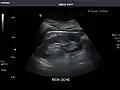

Abdominal Ultrasound (Full Exam)

STRUCTURED REPORT

(Technique: Transabdominal ultrasonography; Device: Toshiba Aplio XG)

Liver: Diffusely homogeneous and normal in echogenicity. No focal mass or contour nodularity. No intrahepatic biliary ductal dilatation.

Portal Vein: Patent main portal vein.

Gallbladder: No stones, wall thickening, or pericholecystic fluid.

Common Bile Duct: Nondilated measuring 1.3 mm at the level of the porta hepatis.

Pancreas: Visualized portions unremarkable.

Spleen: Normal in size.

Kidneys: Right and left kidneys measure 11.5 cm and 12 cm in length respectively. No hydronephrosis. Small left lower pole kidney cyst.

Ascites: None.

Aorta: Visualized portions normal in caliber, 16 x 15 mm.

IVC: Normal.

IMPRESSION:

Normal abdominal ultrasound.